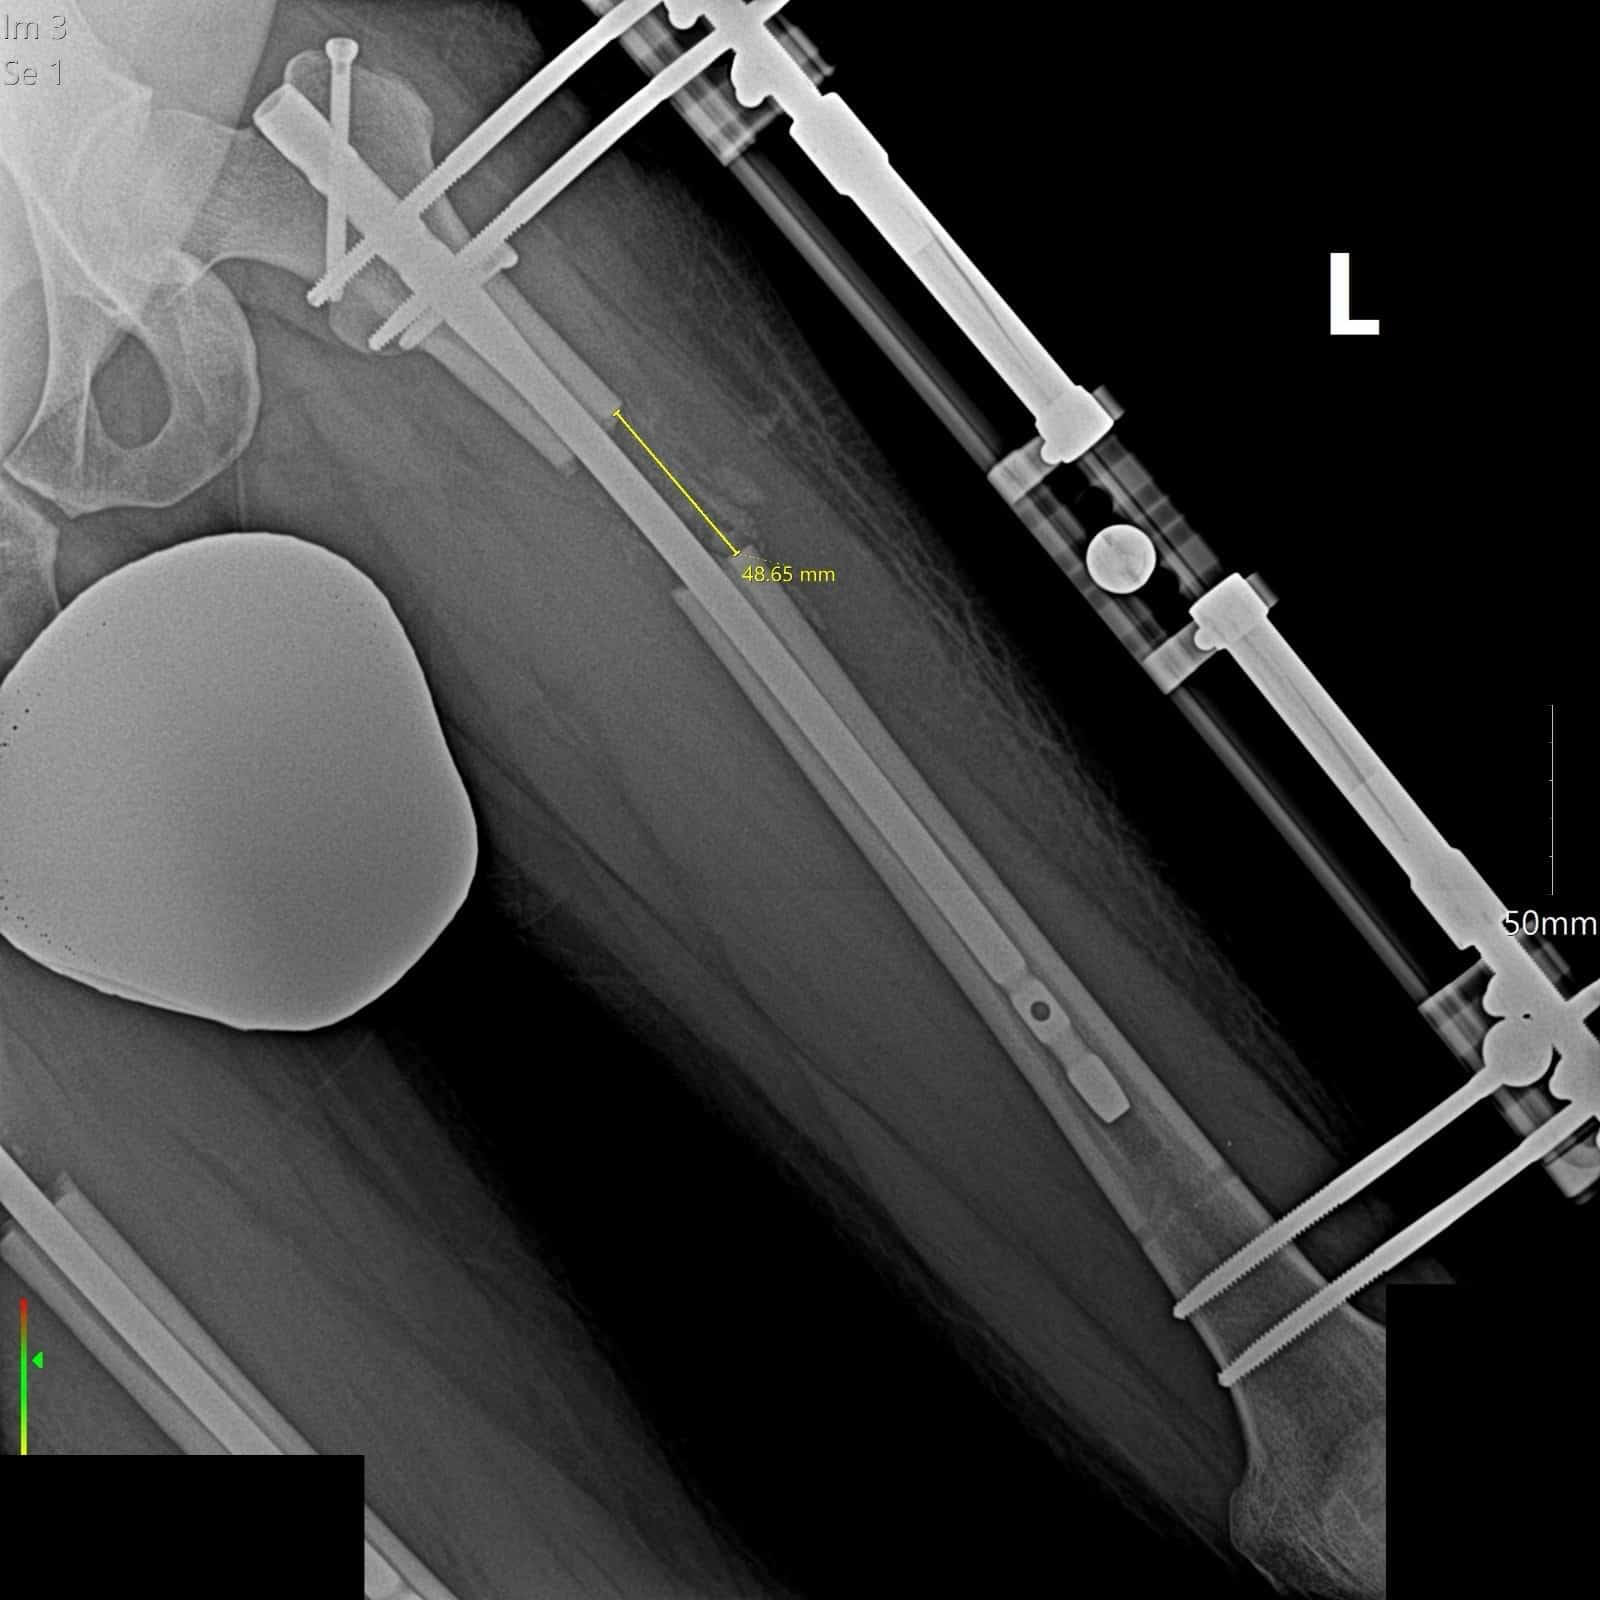

The lengthening over nail starts 5 days after surgery if you have the femur lengthening. For the tibia lengthening, the patient starts lengthening 7 days after surgery. The start of the lengthening may vary depending on the situation of the patient.

After discharging from the hospital, the lengthening phase starts. Throughout the limb lengthening process, it is essential for the patient to undergo physical therapy and receive expert medical support. For example, with an 8 cm target extension (1 mm per day extension), the patient is finished with the complete extension in 80 days.

The recovery timeline depends on how many centimeters the bone is lengthened. On average, the external fixator is removed a few weeks after the desired length is reached, while the internal nail remains until the new bone fully heals. Follow-up visits and X-rays are required during the healing phase to ensure the bone is forming correctly.

After the LON method surgery, the patient starts lengthening approximately 5-7 days later. Following this, physiotherapy sessions commence, accompanied by doctor visits every 2 weeks, and X-Rays taken every 10-15 days. These steps enable the doctor to measure the extent of the lengthening and provide an assessment. Once patients reach their targeted goal, the removal process takes place, initiating the subsequent recovery phase.